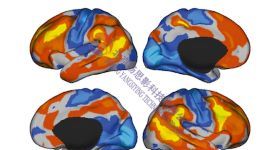

思影科技将于2025年6月25日--6月29日(周三—周日)在上海举办第一百四十六届磁共振脑影像基础班(详见课表安排...

思影科技将于2025年6月25日--6月29日(周三—周日)在上海举办第一百四十六届磁共振脑影像基础班(详见课表安排...